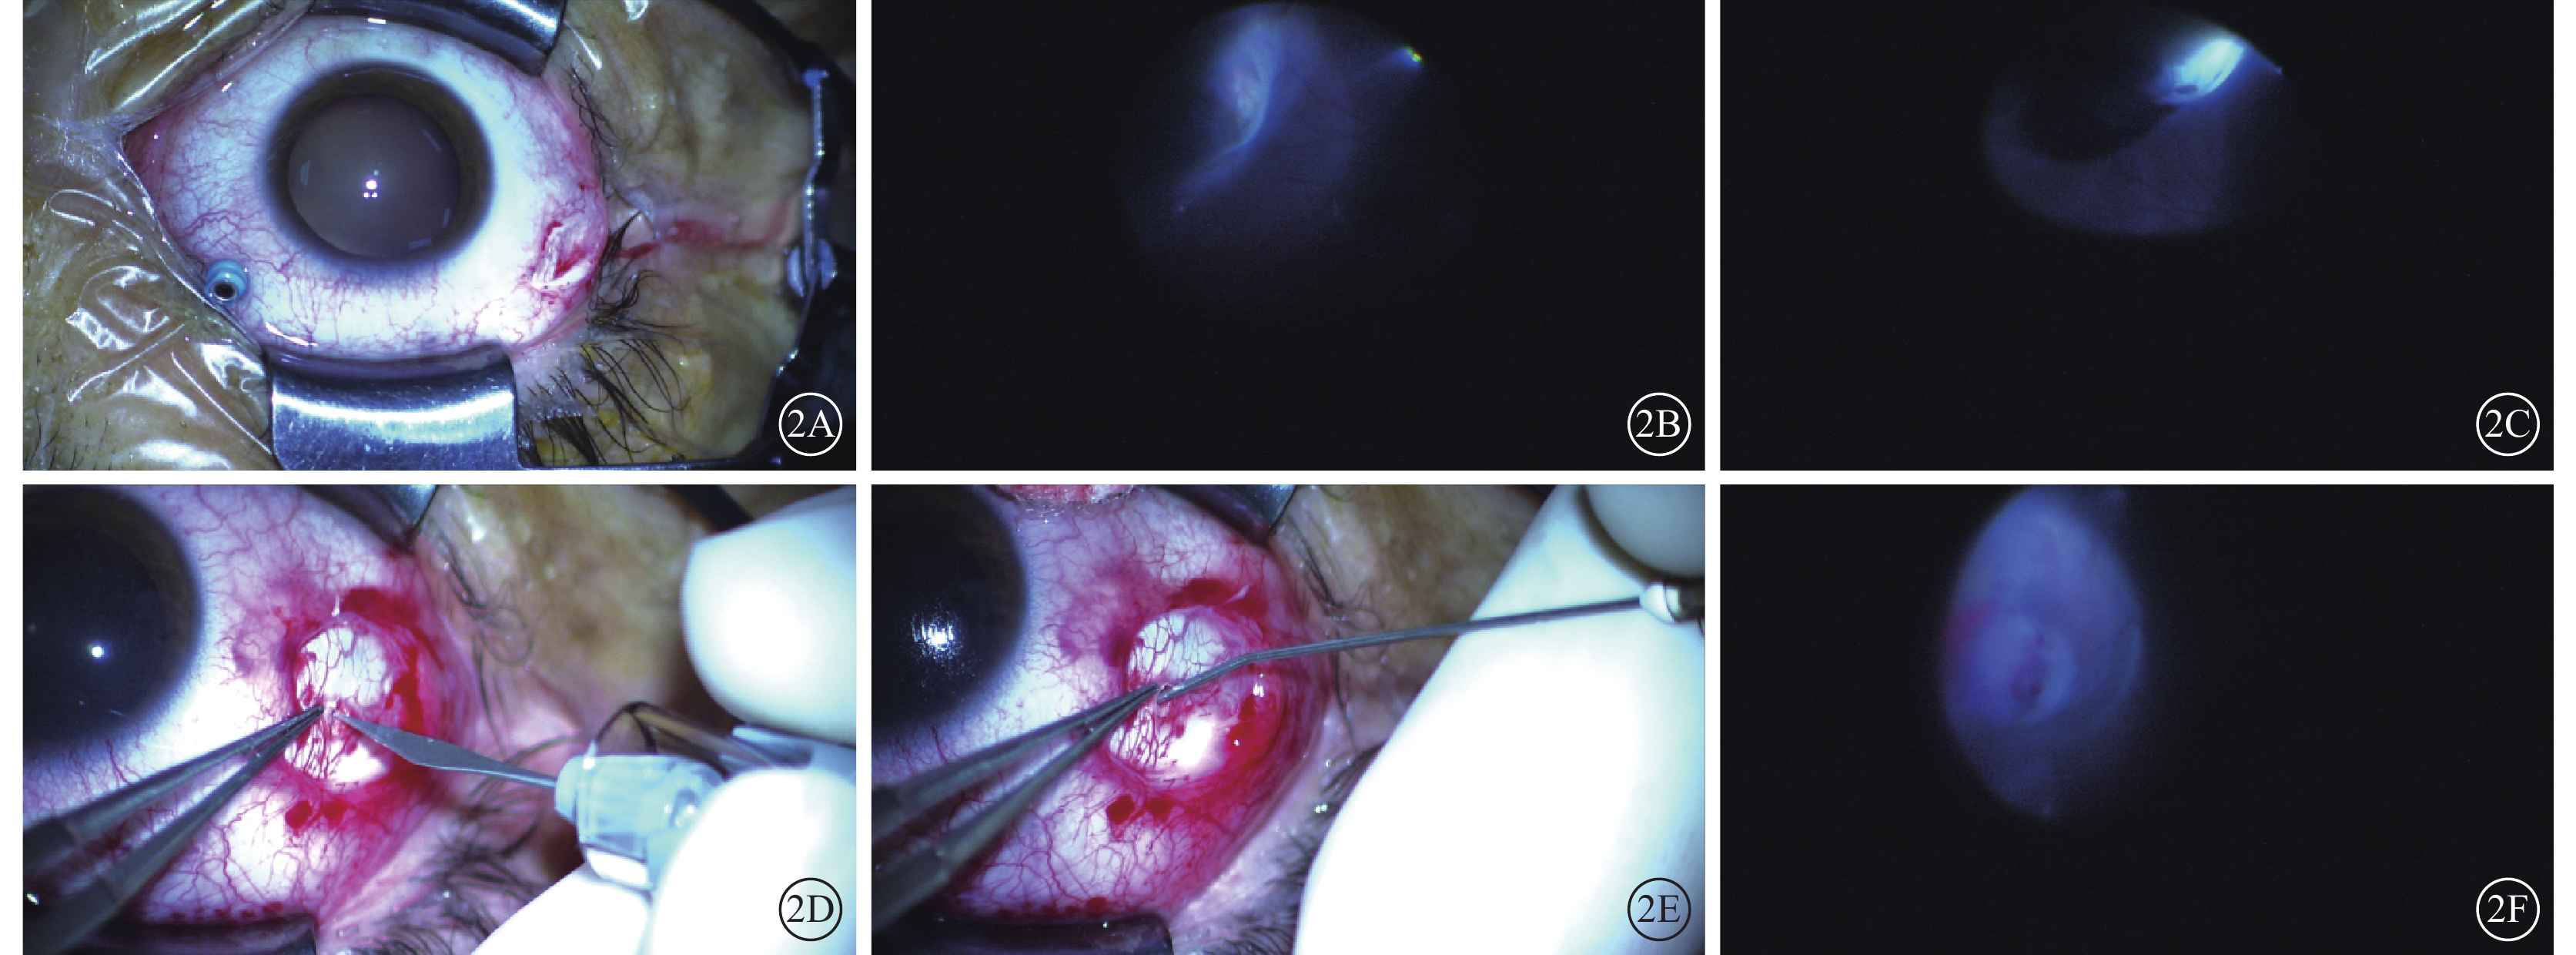

所有患眼在廣域顯微鏡帶內照明系統輔助下行脈絡膜上腔注射透明質酸鈉墊壓手術。手術均由同一位具有豐富手術經驗的醫師完成。患眼經2%利多卡因球后麻醉,在手術顯微鏡下于睫狀體平坦部距角鞏膜緣3.5 mm處并避開裂孔所在象限穿刺25G套管(圖2A),插入光纖照明,放置非接觸廣角系統,仔細檢查全視網膜,尋找視網膜裂孔及變性區(圖2B)并進行定位。對應視網膜裂孔處先行鞏膜外冷凍(圖2C),再根據視網膜脫離隆起較高區域選擇放液部位穿刺放出適量視網膜下液;在裂孔所在象限于兩條直肌之間,距角鞏膜緣6~8 mm處做4~6 mm結膜小切口,分離Tenon’s囊暴露其下鞏膜,做1~2 mm鞏膜板層小切口,分離剩余板層鞏膜(圖2D)。待恰巧穿透鞏膜后,應用自帶鈍性針頭將醫用透明質酸鈉凝膠(德國Bausch Lomb公司)置入鞏膜下、脈絡膜上腔(圖2E)。在顯微鏡直視下緩慢將透明質酸鈉推注入脈絡膜上腔,待顯微鏡下觀察到脈絡膜形成局限性嵴樣隆起并確認視網膜裂孔位于該嵴上(圖2F)后拔出鈍性針頭,8-0可吸收線縫合鞏膜切口及結膜切口各1針。再次在顯微鏡直視下檢查視網膜,必要時對裂孔再行激光光凝以加固裂孔周圍視網膜,最后拔出鞏膜穿刺套管。手術結束后囑患者向裂孔方側臥休息2周,確保裂孔始終呈低位。手術后1周內根據復查情況安排患者行視網膜激光光凝進一步加固裂孔周圍視網膜。

圖2

手術操作圖。2A示于睫狀體平坦部距角鞏膜緣3.5 mm處穿刺25G套管;2B示顯微鏡下檢查全視網膜,定位視網膜裂孔;2C示顯微鏡下對視網膜裂孔行鞏膜外冷凍;2D示在視網膜裂孔區域做2 mm鞏膜板層切口,分離剩余板層鞏膜;2E示通過自帶鈍性針頭將醫用透明質酸鈉凝膠置入鞏膜下及脈絡膜上腔;2F示顯微鏡下確認脈絡膜形成局限性嵴樣隆起且視網膜裂孔位于該嵴上

圖2

手術操作圖。2A示于睫狀體平坦部距角鞏膜緣3.5 mm處穿刺25G套管;2B示顯微鏡下檢查全視網膜,定位視網膜裂孔;2C示顯微鏡下對視網膜裂孔行鞏膜外冷凍;2D示在視網膜裂孔區域做2 mm鞏膜板層切口,分離剩余板層鞏膜;2E示通過自帶鈍性針頭將醫用透明質酸鈉凝膠置入鞏膜下及脈絡膜上腔;2F示顯微鏡下確認脈絡膜形成局限性嵴樣隆起且視網膜裂孔位于該嵴上

所有患眼在廣域顯微鏡帶內照明系統輔助下行脈絡膜上腔注射透明質酸鈉墊壓手術。手術均由同一位具有豐富手術經驗的醫師完成。患眼經2%利多卡因球后麻醉,在手術顯微鏡下于睫狀體平坦部距角鞏膜緣3.5 mm處并避開裂孔所在象限穿刺25G套管(圖2A),插入光纖照明,放置非接觸廣角系統,仔細檢查全視網膜,尋找視網膜裂孔及變性區(圖2B)并進行定位。對應視網膜裂孔處先行鞏膜外冷凍(圖2C),再根據視網膜脫離隆起較高區域選擇放液部位穿刺放出適量視網膜下液;在裂孔所在象限于兩條直肌之間,距角鞏膜緣6~8 mm處做4~6 mm結膜小切口,分離Tenon’s囊暴露其下鞏膜,做1~2 mm鞏膜板層小切口,分離剩余板層鞏膜(圖2D)。待恰巧穿透鞏膜后,應用自帶鈍性針頭將醫用透明質酸鈉凝膠(德國Bausch Lomb公司)置入鞏膜下、脈絡膜上腔(圖2E)。在顯微鏡直視下緩慢將透明質酸鈉推注入脈絡膜上腔,待顯微鏡下觀察到脈絡膜形成局限性嵴樣隆起并確認視網膜裂孔位于該嵴上(圖2F)后拔出鈍性針頭,8-0可吸收線縫合鞏膜切口及結膜切口各1針。再次在顯微鏡直視下檢查視網膜,必要時對裂孔再行激光光凝以加固裂孔周圍視網膜,最后拔出鞏膜穿刺套管。手術結束后囑患者向裂孔方側臥休息2周,確保裂孔始終呈低位。手術后1周內根據復查情況安排患者行視網膜激光光凝進一步加固裂孔周圍視網膜。

圖2

手術操作圖。2A示于睫狀體平坦部距角鞏膜緣3.5 mm處穿刺25G套管;2B示顯微鏡下檢查全視網膜,定位視網膜裂孔;2C示顯微鏡下對視網膜裂孔行鞏膜外冷凍;2D示在視網膜裂孔區域做2 mm鞏膜板層切口,分離剩余板層鞏膜;2E示通過自帶鈍性針頭將醫用透明質酸鈉凝膠置入鞏膜下及脈絡膜上腔;2F示顯微鏡下確認脈絡膜形成局限性嵴樣隆起且視網膜裂孔位于該嵴上

圖2

手術操作圖。2A示于睫狀體平坦部距角鞏膜緣3.5 mm處穿刺25G套管;2B示顯微鏡下檢查全視網膜,定位視網膜裂孔;2C示顯微鏡下對視網膜裂孔行鞏膜外冷凍;2D示在視網膜裂孔區域做2 mm鞏膜板層切口,分離剩余板層鞏膜;2E示通過自帶鈍性針頭將醫用透明質酸鈉凝膠置入鞏膜下及脈絡膜上腔;2F示顯微鏡下確認脈絡膜形成局限性嵴樣隆起且視網膜裂孔位于該嵴上